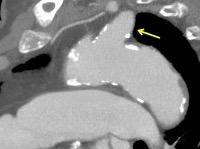

Aneurisma aórtico de localización poco habitual

Edad: 40-50 años

3% segregan catecolaminas.

(En el área Paravertebral +/-50%.)

Intenso realce con el contraste.

32 años .Preeclampsia a los 19. Hipertensión no controlada. Masa paravertebral sólida que se realza intensamente con afectación ósea.

Yue Y t al. Asymptomatic left posterior mediastinal functional Paraganglioma. A case report. Medicine . 2019